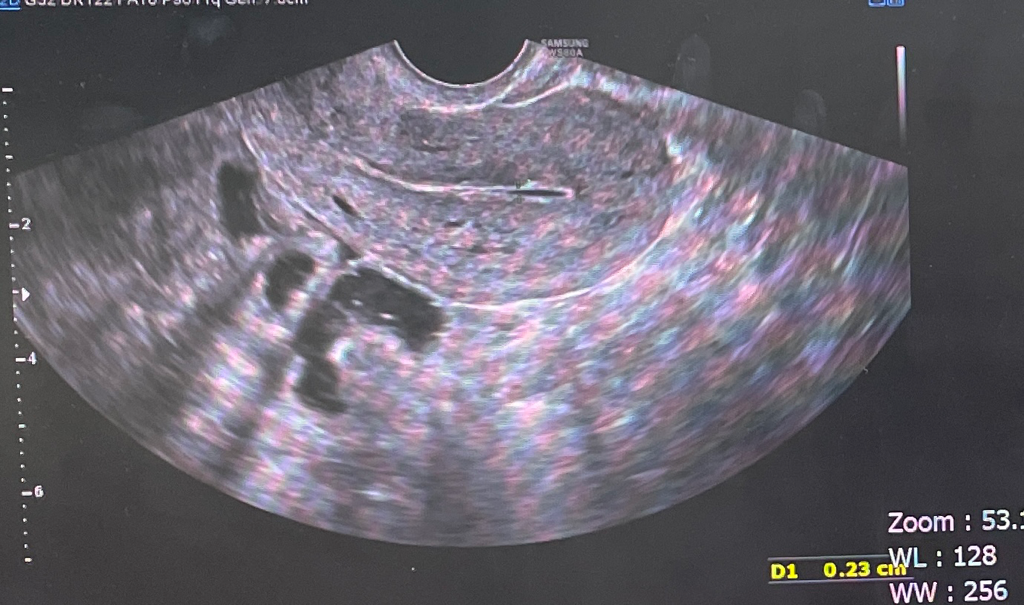

2년전 난소기형종 수술 후 초음파 봐주세요ㅠ

다시 재발한건가요? 자궁 근처에 보이는 검은색 병변이 혹시 종양의 재발인것이 아닌지 초음파를 볼 줄 몰라서요ㅠㅠ 저,고음영이 같이 보이는게 이상한느낌인데

아니라면 저 부분은 뭘까요?

초음파를 직접 본것은 아니지만 일반적으로 보이는 장의 음영입니다. 난소기형종의 가능성은 매우 낮아보이면 산부인과 진료 시 확인하는 것이 정확하겠습니다.